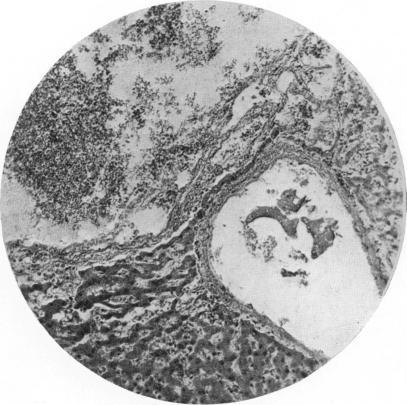

Parsons L G, Ebbs J H

Arch Dis Child. 1940;15(83):129-58. doi: 10.1136/adc.15.83.129.